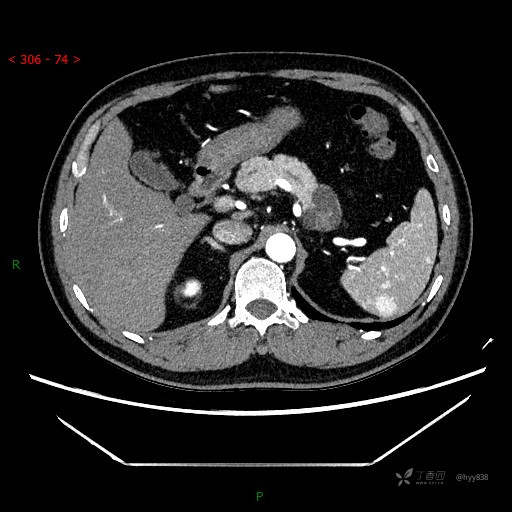

增强动脉期